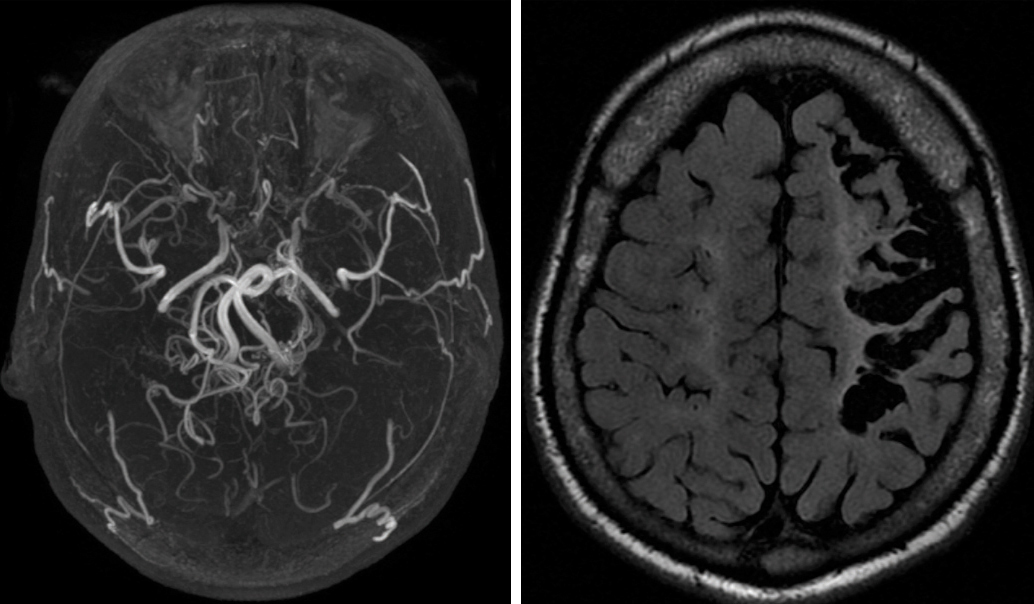

Quel est votre diagnostic ?

Il s'agit d'une atteinte vasculaire cérébrale de type Moya Moya avec séquelle d'accident ischémique cérébral sylvien G chez un patient drépanocytaire (imagerie et angiographie par résonance magnétique). Les atteintes vasculaires cérébrales concernent principalement les patients drépanocytaires homozygotes. Les accidents ischémiques cérébraux des patients homozygotes surviennent principalement dans l'enfance, avec des récidives à tout âge, largement conditionnées par l'existence d'une vasculopathie sténosante. Celle-ci touche principalement les terminaisons des carotides internes, les artères cérébrales antérieures, les cérébrales moyennes, et conduit à un réseau de revascularisation anastomotique particulièrement fragile que l'on appelle la Moya Moya (par analogie à la forme asiatique). Ce réseau contre-indique tout traitement anticoagulant ou antiagrégant du fait du risque hémorragique qu'il comporte. Ainsi, lors d'un accident ischémique aigu chez un patient homozygote, il faut éliminer préalablement une Moya Moya par une angiotomodensitométrie ou une angiographie par résonance magnétique avant de proposer une éventuelle fibrinolyse.